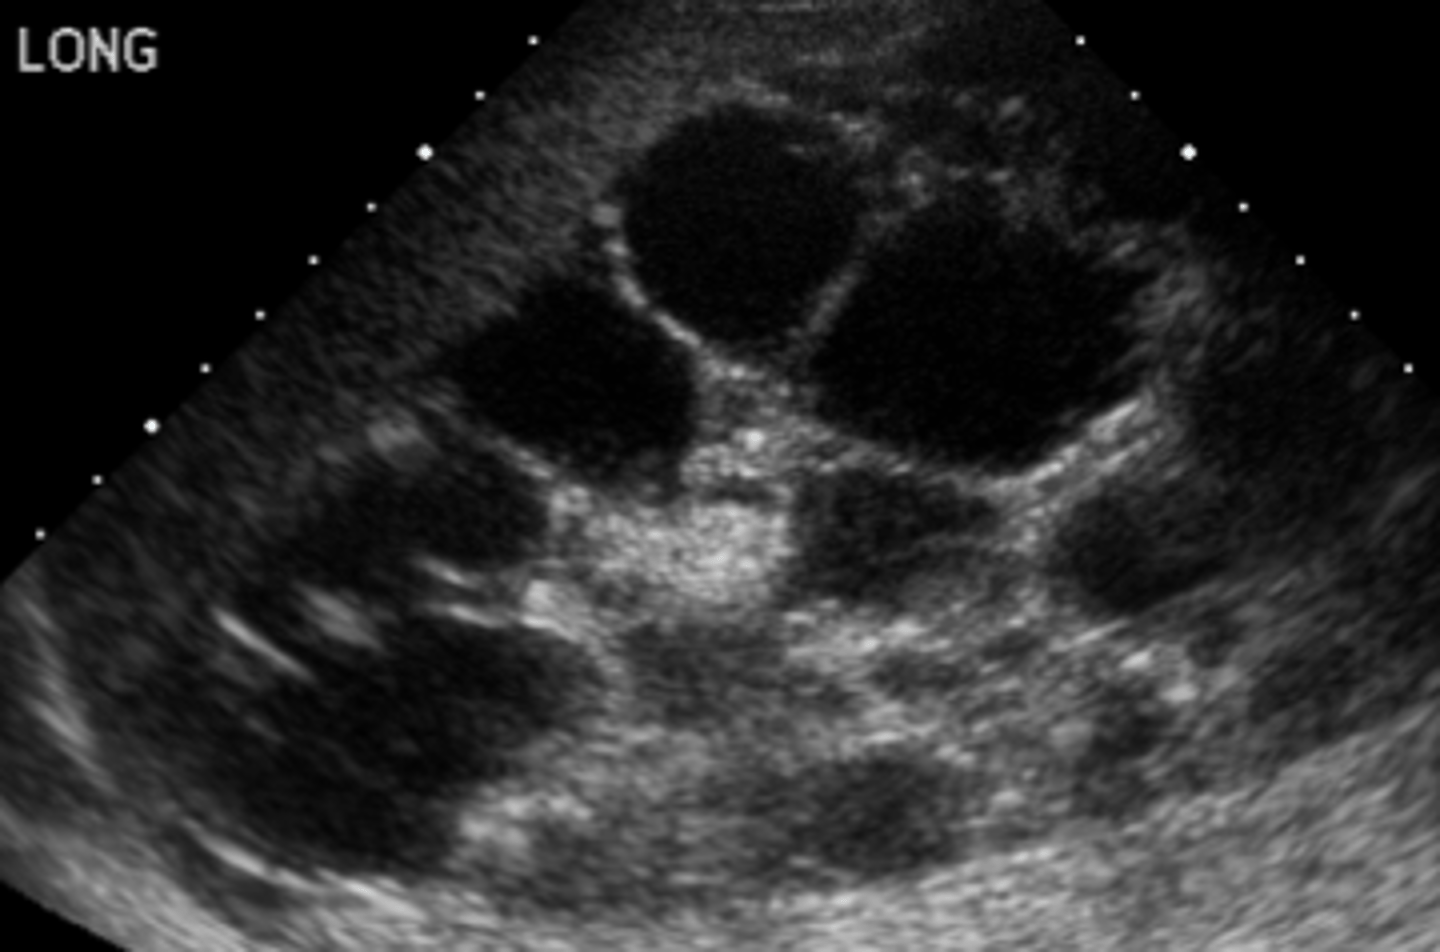

What is the best initial diagnostic test for autosomal dominant PCKD? What is the best overall?

Initial: renal US

Overall: MRI

When does autosomal recessive polycystic kidney disease (PCKD) typically present? What are some common s/sxs?

Often found on the prenatal ultrasound (readily apparent at birth); anatomical abnormalities, HTN within first few months of life, CHF s/sxs, prenatal oligohydramnios (can produce anomalies such as pulmonary hypoplasia, Potter facies, etc.)